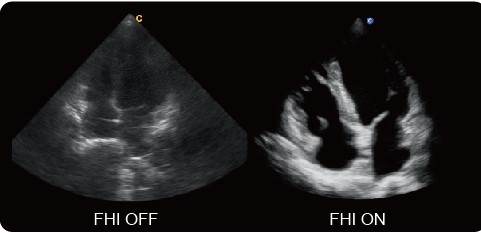

FHI - инновационная технология гармонизации изображений, которая учитывает вес пациента при обработке сигнала. Традиционная тканевая гармоника и фазовая гармоника могут дать недостаточно достоверные результаты, когда глубина проникновения луча увеличена (например, у пациентов с ожирением). Технология FHI повышает диагностические возможности при проведении исследования у пациентов с ожирением и с затрудненной визуализацией.